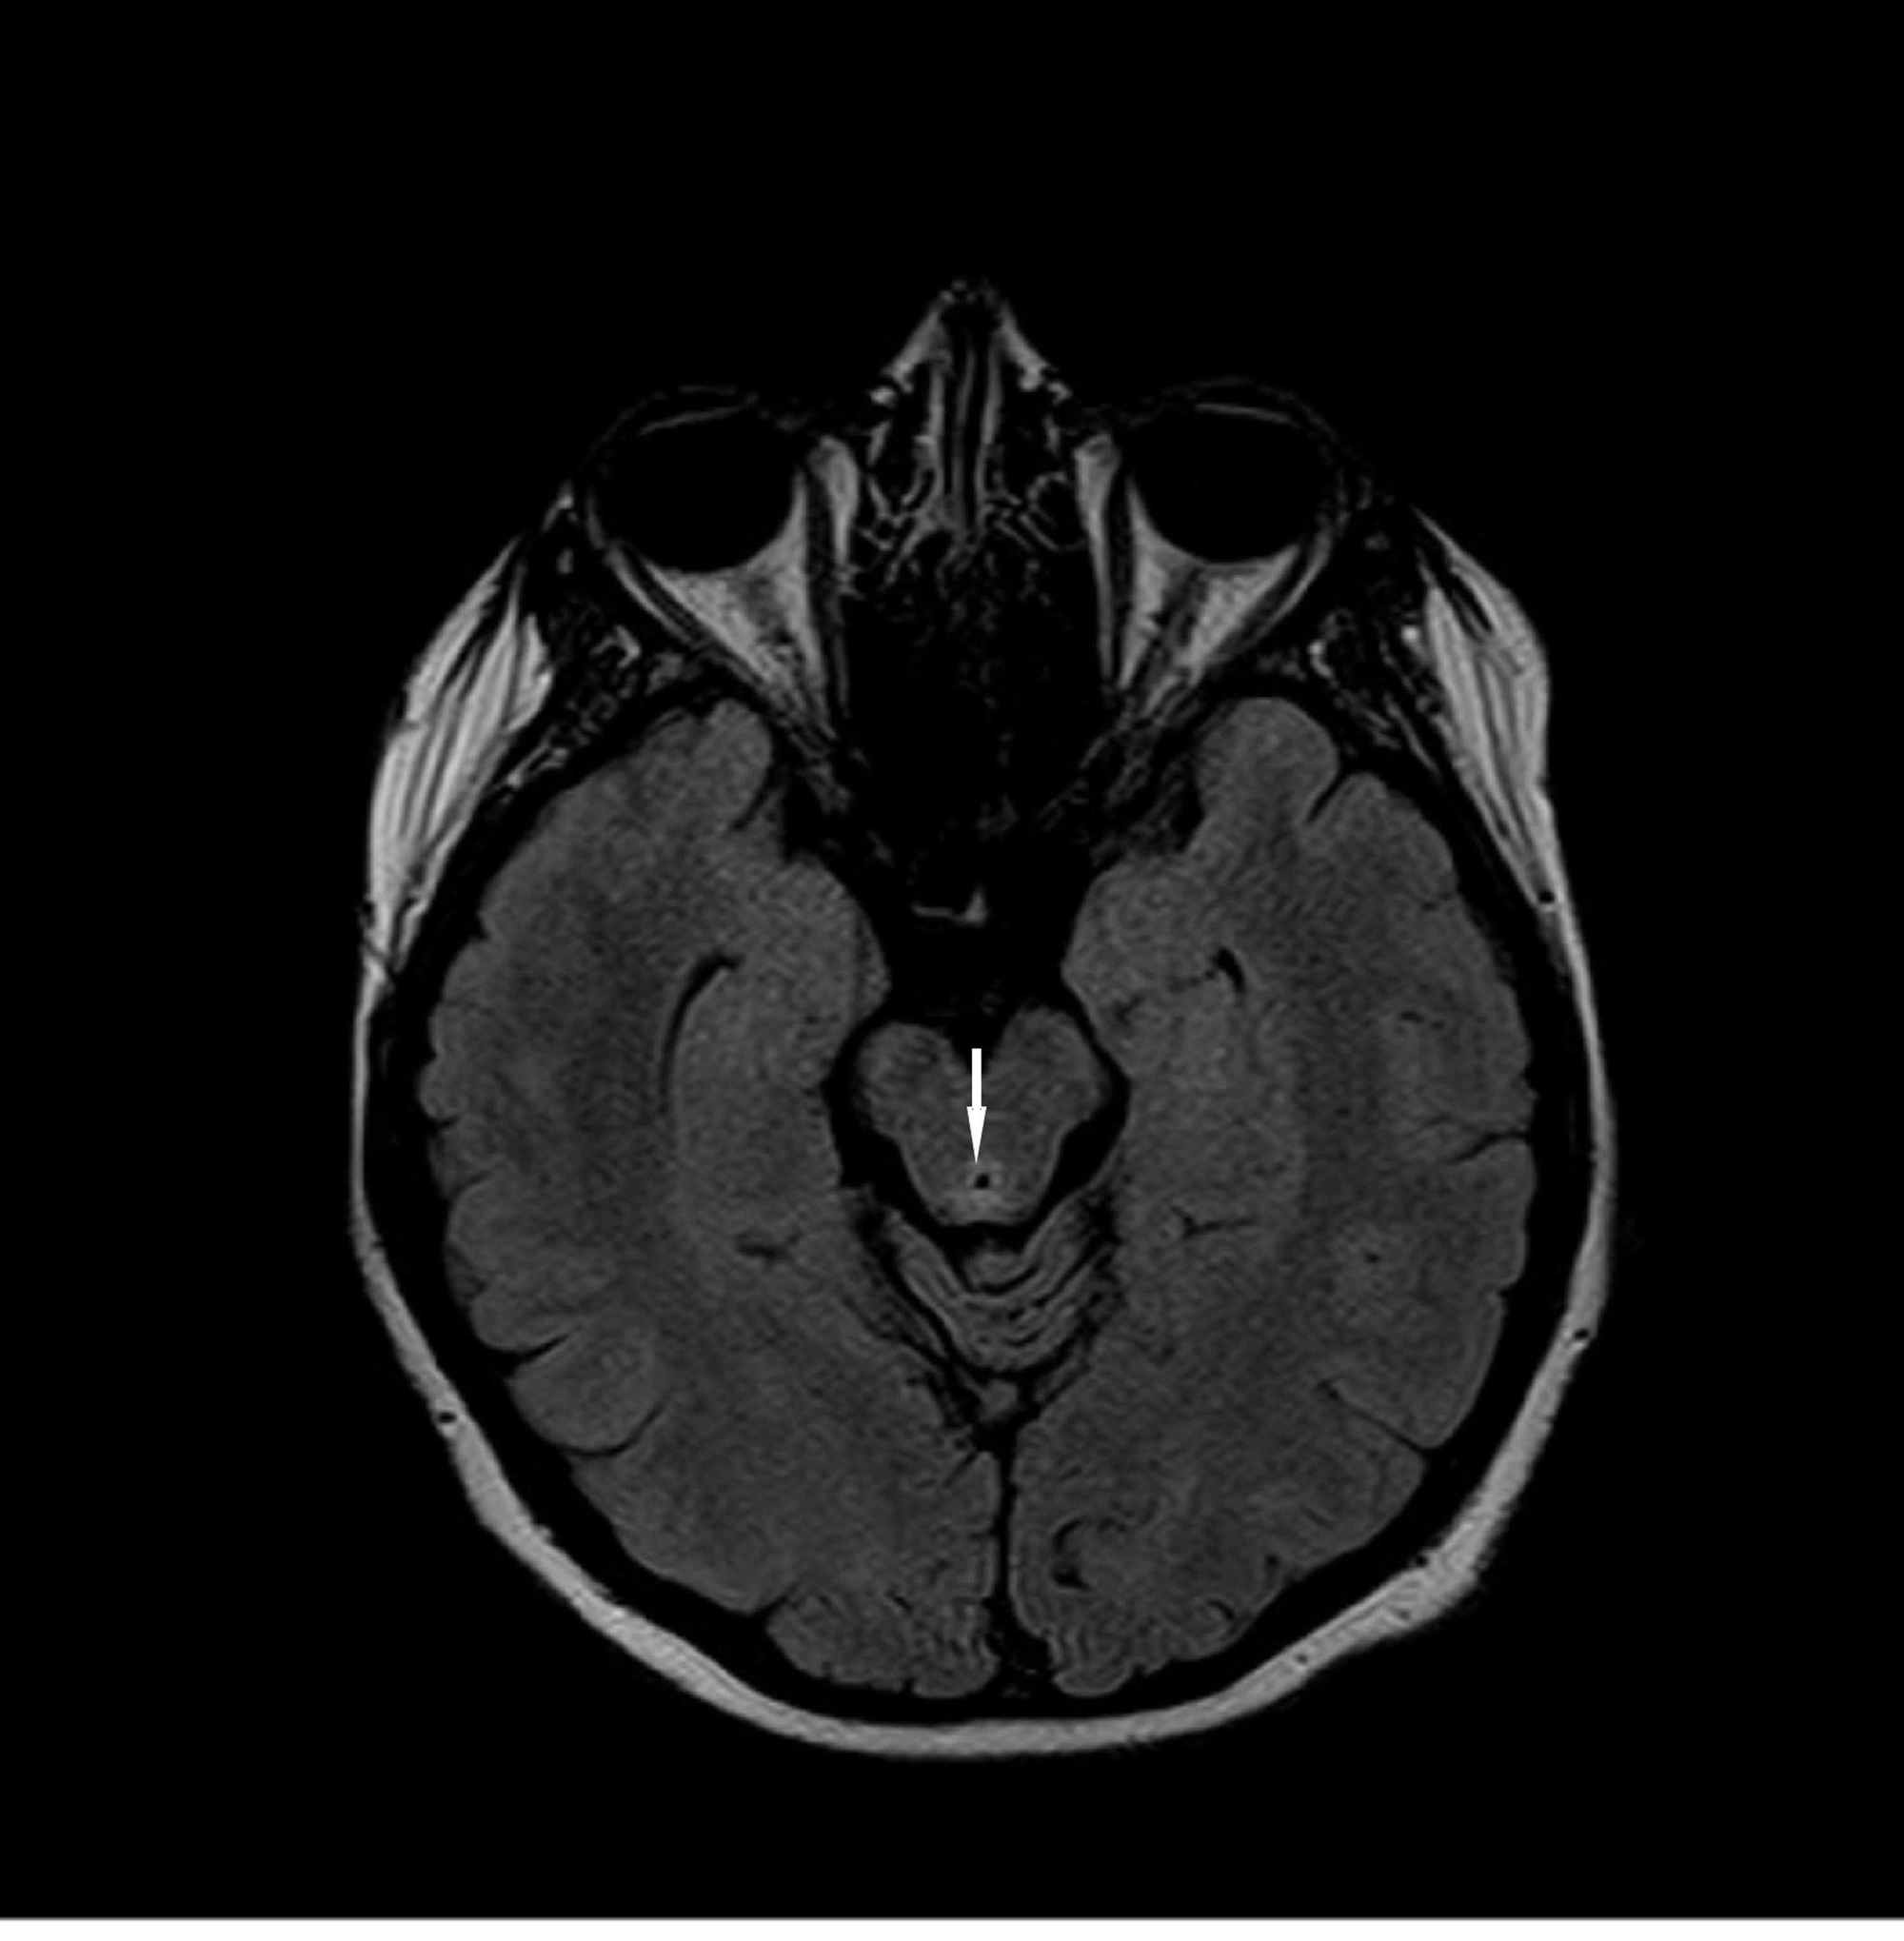

Dr Balaji Anvekar FRCR Vit B12 deficiency MRI brain findings Vitamin B6 Deficiency Brain Mri Methylmalonic acidemia (mma) is a severe, heterogeneous disorder of methylmalonate and cobalamin (cbl; This activity reviews the diagnosis, evaluation, and. For example, the primary symptoms of vitamin b 6 deficiency are neurological, including depression, cognitive decline,. While evidence exists that supplementation of vitamins b6 and b1 might be beneficial for cognition and brain structure, at least in deficient states and. Vitamin B6 Deficiency Brain Mri.